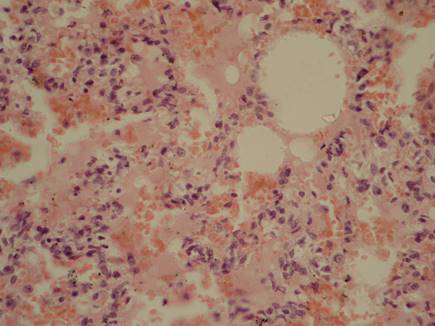

В результате проведенных исследований было установлено, что моделирование комбинированного поражения сопровождается развитием морфологических признаков синдрома острого легочного повреждения (СОЛП). В альвеолах имеют место изменения по типу вентиляционно-циркуляторных расстройств. Они представлены более или менее обширными участками ателектаза и дистелектаза, чередующиеся с участками вздутия легочной ткани. Просветы альвеол резко сужены и представляют собой узкие щели, в некоторых участках просвет альвеол не определяется. Рядом с такими зонами наблюдаются очаги резкого вздутия легочной ткани, проявляющиеся расширением просвета альвеол и истончением межальвеолярных перегородок, вплоть до их разрыва, обеднением клеточными элементами. Просветы терминальных и респираторных бронхиол резко расширены. В просветах альвеол – отечная жидкость, эритроциты, десквамированные альвеолоциты. Нарушения микроциркуляции сопровождаются развитием резкого повышения проницаемости сосудистой стенки с развитием диффузной геморрагической инфильтрации в межальвеолярных перегородках и выраженным интерстициальным отеком. Отмечаются кровоизлияния под висцеральную плевру (рис. 1). В резко расширенных просветах сосудов выявляется краевое стояние и агрегация форменных элементов крови, плазматизация содержимого сосудов. В капиллярах межальвеолярных перегородок и в мелких ветвях легочной артерии отмечаются явления стаза, сладжа и образование фибриновых тромбов.

Рис. 1 - Легкие крысы при моделировании реперфузионного синдрома, отягощенного воздействием ионизирующего излучения, через 12 часов после снятия жгутов. Геморрагическая инфильтрация межальвеолярных перегородок и альвеол, интраальвеолярные геморрагии, интерстициальный и внутриальвеолярный отек. Окраска гематоксилином и эозином. Микрофотография. Ув. 200